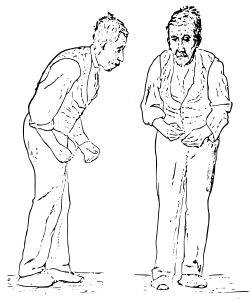

Doença de Parkinson: esta doença neurodegenerativa é caracterizada pela morte de neurónios dopaminérgicos em certas regiões do cérebro, o que leva a problemas locomotores.[60] Não se sabendo bem quais os circuitos responsáveis quais os circuitos neuronais responsáveis pelo planeamento motor e pela seleção de ações afetado nestas doenças, tendo sido descritos dois modelos responsáveis por obter respostas diferentes no funcionamento motor: a via direta e a via indireta. Para determinar o modelo mais correto, utilizaram-se ferramentas optogenéticas, ativando as vias. Foi observado que a excitação da via indireta provocava sintomas de Parkinson, como o aumento de imobilização e redução do início de novas ações locomotoras. Pelo contrário, ao ativar a via direta num modelo de ratinho com Parkinson, verificou-se uma melhoria dos sintomas comuns nesta doença. Assim, neste estudo comprovou-se que a modulação do circuito da via direta pode ser usado como estratégia terapêutica para melhorar a deficiência motora.[61]

A estimulação cerebral profunda tem sido estudada como outra possível forma de tratamento para esta doença. Sendo necessária uma elevada precisão na colocação correta dos elétrodos no cérebro, a optogenética tem ajudado melhorar a especificidade dos circuitos neuronais e também a perceber melhor quais as células neuronais relevantes para este processo. Utilizando ratinhos modelo com doença de Parkinson, foram demonstrados efeitos terapêuticos ao estimular diretamente os axónios dos neurónios projetados para a região do núcleo subtalâmico.[60]